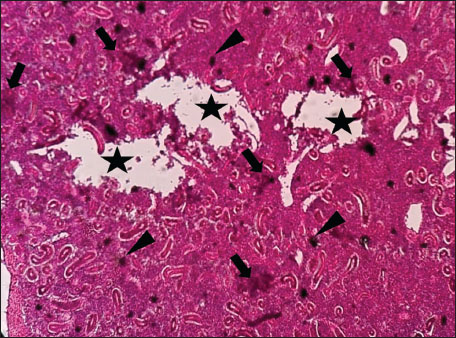

ABSTRACTBackground: The Mediterranean Sea has undergone significant ecological changes in recent decades, partly due to the introduction of non-native species. Lagocephalus sceleratus is an invasive Lessepsian species widely distributed in the Mediterranean, increasingly abundant along the Libyan coast, and potentially exposed to chronic environmental stressors. This species represents an important model for baseline pathological assessment in newly colonized marine environments. Aim: This study provides a descriptive histopathological assessment of kidney and gill tissues in adult L. sceleratus to document baseline tissue alterations without inferring direct environmental or pollution-related causation. Methods: A total of 150 adult specimens were collected from four Libyan coastal locations. Tissues were processed using standard histological techniques and evaluated semi-quantitatively (+, ++, +++) for lesion severity. Lesion severity grades were converted into ordinal numerical data and summarized using descriptive statistical approaches only. Results: Kidney tissues exhibited tubular degeneration, Bowman’s capsule dilatation, vascular congestion, extensive melanomacrophage centers (MMCs), and inflammatory lesions. Gill tissues showed disorganization of secondary lamellae, epithelial hyperplasia, edema, aneurysmal dilatations, vascular congestion, and MMC proliferation, some of which were associated with histologically observed parasitic structures. Conclusion: The observed alterations represent descriptive baseline tissue changes and should not be interpreted as direct evidence of pollution or specific environmental stressors. These findings provide reference data for future comparative pathological and ecological studies. Keywords: Lagocephalus sceleratus, Kidney, Gills, Histopathology, Melanomacrophage centers, Invasive species, Mediterranean Sea. IntroductionIn recent decades, the Mediterranean Sea has undergone profound ecological changes driven by the arrival and establishment of non-native marine species. Among these, Lagocephalus sceleratus has emerged as one of the most impactful Lessepsian migrants, due to its rapid geographic expansion, high ecological adaptability, and the presence of the potent neurotoxin tetrodotoxin in its tissues. This species has been widely documented to alter local fish communities, affect fisheries, and pose public health risks, making it an important target for biological and environmental assessment across the region (Katikou et al., 2022; Christidis et al., 2024). Fish are widely recognized as sensitive biological organisms in aquatic ecosystems, particularly in coastal habitats that are exposed to anthropogenic pressures such as industrial effluents, agricultural runoff, and untreated wastewater (Pinna et al., 2023). Among fish organs, the gills and kidneys are commonly regarded as sensitive to environmental stress, as they respond to physiological and pathological changes under environmentally suboptimal conditions. The gills, due to their large surface area and continuous exposure to surrounding water, are often the first tissues to exhibit structural alterations when fish encounter pollutants (Shahid et al., 2022). Histopathological changes in gills observed in polluted environments include epithelial lifting, lamellar fusion, hyperplasia, increased mucous cell density, and focal necrosis, which collectively reflect early physiological stress and potential compromise of respiratory function (Osman, 2010; Shahid et al., 2022). Similarly, the kidneys play crucial roles in osmoregulation, excretion of metabolic waste, and detoxification, making them highly vulnerable to chronic or systemic toxic effects (Wahidi et al., 2025). Documented renal lesions associated with chemical exposure include tubular deterioration, glomerular shrinkage, interstitial edema, and infiltration of inflammatory cells. These structural alterations often coincide with underlying biochemical disruptions, such as oxidative stress, impaired detoxification pathways, and activation of apoptotic mechanisms (Bernet et al., 1999; Authman, 2015). Despite the growing body of research on the ecological and toxicological implications of L. sceleratus, detailed histopathological assessments of this species remain scarce, especially in the southern Mediterranean basin, where environmental conditions and pollution profiles may differ from those in other regions. To date, detailed tissue-level studies of L. sceleratus from the southern Mediterranean are lacking, which limits the understanding of how this invasive species responds physiologically to local environmental stressors (Shakman et al., 2019; Ulman et al., 2021; Mohmmed et al., 2023). Accordingly, the present study aims to provide a comprehensive descriptive evaluation of histopathological changes in the kidneys and gills of L. sceleratus. The study is designed as a baseline histopathological assessment, focusing on tissue-level alterations without establishing causal links to environmental pollution or physicochemical stressors. By documenting structural aberrations and pathological features, this study contributes reference data for future monitoring and comparative studies in Mediterranean coastal ecosystems. Materials and MethodsSample designA total of 150 adult specimens of L. sceleratus, including both sexes, were collected from four Libyan coastal locations: Talamitha (n=39), Susah (n=34), Ain El-Ghazala (n=30), and Khalij Al-Bambah (n=47). Fish ranged in total length from 51 to 66 cm and in weight from 1.5 to 3.5 kg. Only apparently healthy adults were included, while juveniles were excluded to avoid age-related histopathological variation. Sampling was conducted opportunistically with assistance from local fishermen. All specimens were collected within a comparable seasonal window to minimize seasonal histopathological variability. Sex was recorded when possible; however, sex-based histopathological comparisons were not performed, as this was beyond the descriptive scope of the study. Fish were transported on ice at +4°C and examined in the Pathology Laboratory, Faculty of Veterinary Medicine, Omar Al-Mukhtar University (Mohmmed et al., 2023). Specimens were collected from a range of depths (0.5–70 m), with the majority from shallow waters (<10 m) and a subset (approximately 50 fish) from deeper locations (>30 m). Environmental physicochemical parameters such as temperature, salinity, and dissolved oxygen were not measured; therefore, no direct associations between histopathological findings and environmental variables were assessed. Tissue processing and histopathological examinationTissue specimens were fixed in 10% neutral buffered formalin for 24 hours. Following fixation, the samples were transferred to 70% ethanol for storage at room temperature. Subsequently, the tissues were processed for routine histopathological examination following standard procedures (Paul and Chanda, 2017). Paraffin embedding was performed, and 5 µm-thick sections were prepared using a microtome. Sections were stained with hematoxylin and eosin (H&E) and examined under a light microscope. Photomicrographs of representative lesions were captured using a high-resolution digital camera. Histopathological alterations were evaluated using a semi-quantitative scoring system adapted from Hose et al. (1996), Moshaie-Nezhad et al. (2021), and Alshailabi et al. (2023), where lesion severity was graded as mild (+), moderate (++), or severe (+++). Lesion severity grades (+, ++, +++) were converted into ordinal numerical values (1–3) for descriptive summarization of lesion severity. Due to the descriptive baseline nature of the study and the absence of a reference control group, inferential statistical comparisons were not emphasized or applied. Lesion severity scores were therefore summarized descriptively to avoid overinterpretation of the findings. Scoring was performed independently by two experienced observers, and representative lesions were confirmed across three sections per organ to ensure consistency. Tissues with visible parasitic structures were described separately from non-parasitized tissues to avoid conflating parasite-associated lesions with non-specific tissue alterations. The functional implications of the observed lesions were interpreted in accordance with Flores-Lopes and Thomaz (2011). Ethical approvalAll animal experiments conducted in this study were approved by the Ministry of Higher Education & Scientific Research and the Libyan National Committee for Biosafety & Bioethics, Libya. All procedures were performed in accordance with the relevant ethical guidelines, with session number 21/CH/25, dated 26/05/2021. ResultsHistopathological examination of the kidneyHistopathological examination of the kidney tissues of L. sceleratus revealed multiple alterations. Prominent melanomacrophage centers (MMCs), necrotic areas, dilatation of Bowman’s capsules, and vacuolar degeneration were observed (Fig. 1), associated with interstitial lymphohematopoietic tissue (Fig. 2). Dilated and congested blood vessels and extensive MMCs were also noted (Fig. 3). Renal degeneration surrounding lymphohematopoietic tissue, large clusters of MMCs, and thickened, congested vessel walls within fibrotic areas were evident (Fig. 4). Atrophic renal degeneration with necrotic and vacuolar changes was observed (Fig. 5). Severe inflammatory infiltration of lymphatic cells and granulomas with necrotic centers, surrounded by fibrous tissue, was detected (Figs. 6–7).

Fig. 2. Histopathology of the kidney in an adult L. sceleratus showing renal degeneration with necrotic areas (stars), severe MMCs (head arrows), and interstitial lymphohematopoietic tissue (thick arrows). ×40 H&E.